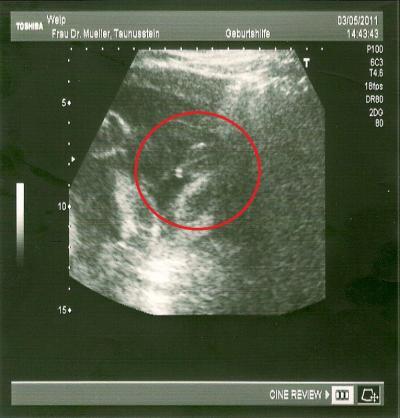

Hallo Ihr Lieben, Asche auf mein Haupt das ich mich solang nicht gemeldet hab. Aber leider war weder mein 3D US erwähnenswert ( lief nicht so dolle) noch hab ich so nen schönen Babybauch. Aber die Vorsorge war toll heute, endlich hat sich unser 70-80% Mädchen geoutet *smile* Bild seht Ihr unten und könnt mal raten *g* Leider hab ich auch ne Blasenentzündung und muß jetzt Medis nehmen Nächste Woche dann Zuckertest und am Wochenende fängt mein GVK an. Liebe Grüße Euch allen Dani 26+3

Bild zu Auch mal melden mag :) - Forum für August - Mamis

das wird ein bub oder?

Gute Besserung erstmal! Hätte auch auf nen Jungen getippt!! :-) Los erzähl, was wirds denn nun? Haben wir recht? GLG

schön dass du dich meldest. Ich sehe nicht viel nur diese zwei Striche. Deuten diese nicht auf Schamlippen *amKopfkratz* aber wie gesagt, ich bin ganz schlecht in Ultraschallbilder deuten;) Wünsche dir viel Spass bei GVK:) Liebe Grüße von deiner Patin

Supi, das alles ok ist. Also ich habe lt. Bild auch auf einen Jungen getippt, denn mein US Bild von unserer Prinzessin schaut sehr anders aus. Aber das Wichtigste ist, dass alles gesund ist, gell? LG sonnenschein11